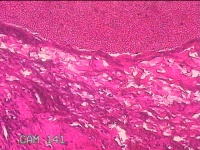

双侧眼睑结节

性别

男

年龄

52岁

临床诊断

眼睑皮赘

一般病史

发现双侧眼睑结节5年余,无疼痛及不适。

标本名称

大体所见

灰白暗红色结节0.8x0.7x0.3cm两个,表面糜烂,切面灰白粉红色,质软。

不具诊断价值。